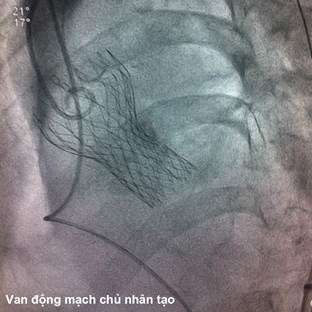

Hình 1: Đánh giá động mạch đùi - chậu bằng phim chụp cản quang

Các thăm dò trước thủ thuật thay van động mạch chủ qua da bao gồm: xét nghiệm công thức máu, hoá sinh máu, điện tâm đồ, siêu âm tim qua thành ngực và qua thực quản, chụp động mạch vành và chụp động mạch đùi cản quang, chụp cắt lớp vi tính đa dãy (MSCT) động mạch chủ ngực - bụng, động mạch đùi chậu. Bệnh nhân có tình trạng thiếu máu nhẹ trước thủ thuật (Hb 98 g/L), chức năng thận bình thường (mức lọc cầu thận 98 mL/phút). Điện tâm đồ có hình ảnh bloc nhánh trái hoàn toàn, tăng gánh tâm thu thất trái. Kết quả siêu âm tim qua thành ngực cho thấy hẹp khít van động mạch chủ, diện tích lỗ van 0,636 cm2, chênh áp tối đa qua van động mạch chủ 67 mmHg, chênh áp trung bình 40,4 mmHg. Hở van động mạch chủ mức độ nhẹ. Đường kính vòng van động mạch chủ 25,2 mm, đường kính đường ra thất trái 24,3 mm, đường kính động mạch chủ ngang qua xoang Valsava 32 mm, đường kính động mạch chủ lên 24,7 mm. Chức năng tâm thu thất trái trong giới hạn bình thường (EF 65%). Đường kính thất trái cuối tâm trương 50 mm. Bệnh nhân có tăng áp lực động mạch phổi mức độ vừa (áp lực động mạch phổi tâm thu 45 mmHg). Chụp động mạch vành có hẹp 40% đoạn giữa động mạch liên thất trước, dòng chảy mạch vành tốt. Chụp cắt lớp vi tính 64 dãy động mạch chủ ngực-bụng cho thấy xơ vữa gây hẹp lan toả động mạch chủ. Động mạch chủ ngực, động mạch chủ bụng trên và dưới động mạch thận có khẩu kính bình thường, ngã ba chủ chậu không hẹp tắc. Hẹp khít động mạch thận hai bên. Động mạch chậu và động mạch đùi phải xoắn vặn, hẹp lan toả, đường kính động mạch đùi phải chỗ hẹp nhất khoảng 5 mm. Động mạch chậu và động mạch đùi trái không hẹp, đường kính động mạch đùi trái chỗ hẹp nhất 6,5 mm. Động mạch dưới đòn trái không hẹp, tắc.

Mặc dù các van sinh học thế hệ mới ngày càng có kích thước nhỏ gọn hơn, tuy nhiên tỉ lệ biến chứng mạch máu vẫn còn cao (khoảng trên 10%)5. Đo kích thước và đánh giá tình trạng hẹp, tắc, xoắn vặn, vôi hoá của mạch máu động mạch đùi, động mạch chậu, động mạch chủ bụng trước thủ thuật, theo phim chụp cắt lớp vi tinh đa dãy, phim chụp mạch cản quang, và siêu âm mạch máu, giữ vai trò rất quan trọng trong việc giảm tỉ lệ biến chứng mạch máu. Đối với bệnh nhân của chúng tôi, đường kính động mạch đùi trái chỗ hẹp nhất là 6,5 mm, trong khi động mạch đùi-chậu phải xoắn vặn và hẹp lan toả. Khác với van Edwards-Sapien, không thể tiến hành đặt CoreValve xuôi dòng qua đường mỏm tim. Do vậy, chúng tôi cũng đã tiến hành đo đạc để sẵn sàng đặt van qua đường động mạch dưới đòn phải hoặc qua đường mở ngực tối thiểu, trong trường hợp không thể tiến hành qua đường động mạch đùi. Tuy nhiên, kích thước động mạch đùi-chậu trái của bệnh nhân hoàn toàn tương thích cho sheath 18 French và thủ thuật được tiến hành thuận lợi, không gặp khó khăn nào liên quan đến đường can thiệp. Dụng cụ đóng động mạch chuyên dụng Perclose (hãng Abbott, Hoa Kỳ) cho phép cầm máu vết chọc mạnh nhanh và hiệu quả. Bệnh nhân của chúng tôi hoàn toàn không gặp phải một biến chứng nào liên quan đến đường vào mạch máu.